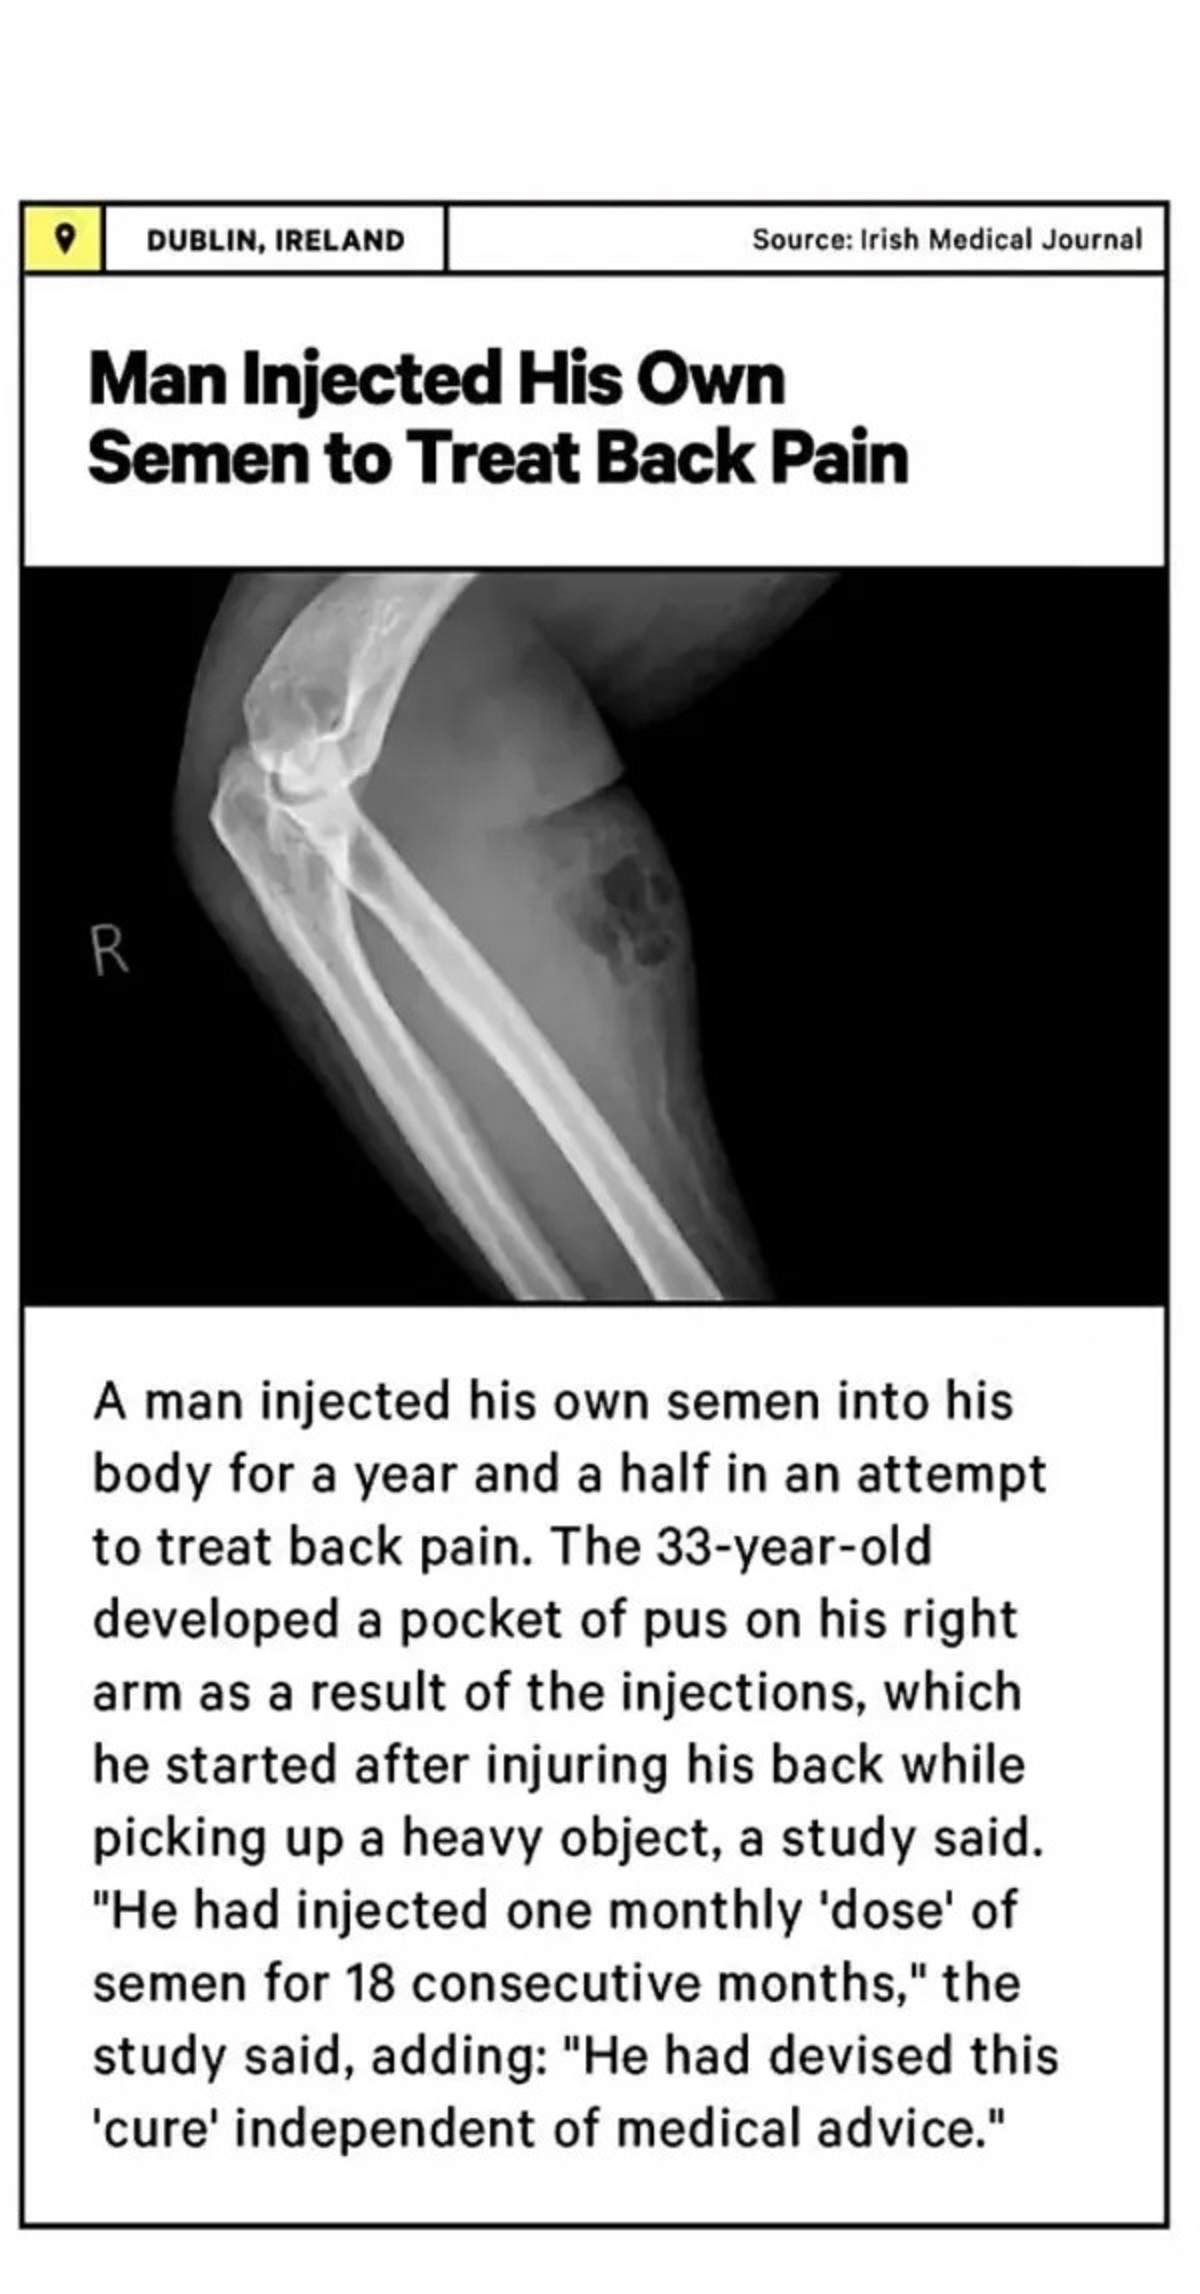

9.